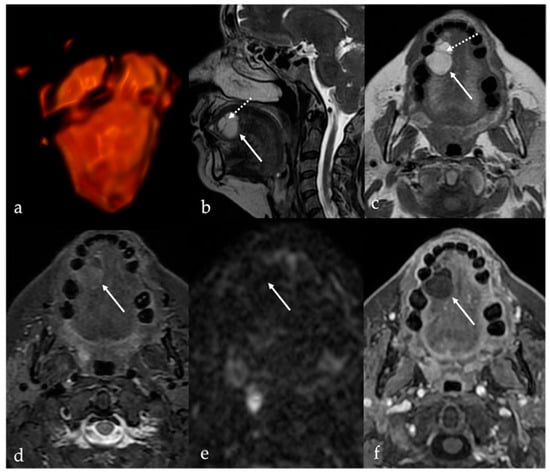

8. Lingual Abscess

9. Lingual Tonsillitis as Manifestation of Infectious Mononucleosis

10. Fatty Atrophy of the Tongue (Chronic Hemilingual Denervation)

| Abscess [17] | CT, MRI: peripheral enhancement MRI: core of the lesion shows high SI on DWI, and restricted diffusion with low values on ADC map | Submucosal malignancy |

| Lingual tonsillitis in infectious mononucleosis [18] | CT, MRI: symmetric tonsil enlargement, retention cysts, and “linear or columnar pattern” of enhancement (features of benign tonsillar hypertrophy) | Lingual tonsil lymphoma |

| Chronic hemilingual denervation [19] | Fatty atrophy of the affected hemilingual muscles with volume loss and lingual deviation, without mass-like lesion CT: −83 to −134 HU (like subcutaneous fat tissue) MRI: high T1 and T2 SI, fat saturation signal | Lipoma, angiomyolipoma |